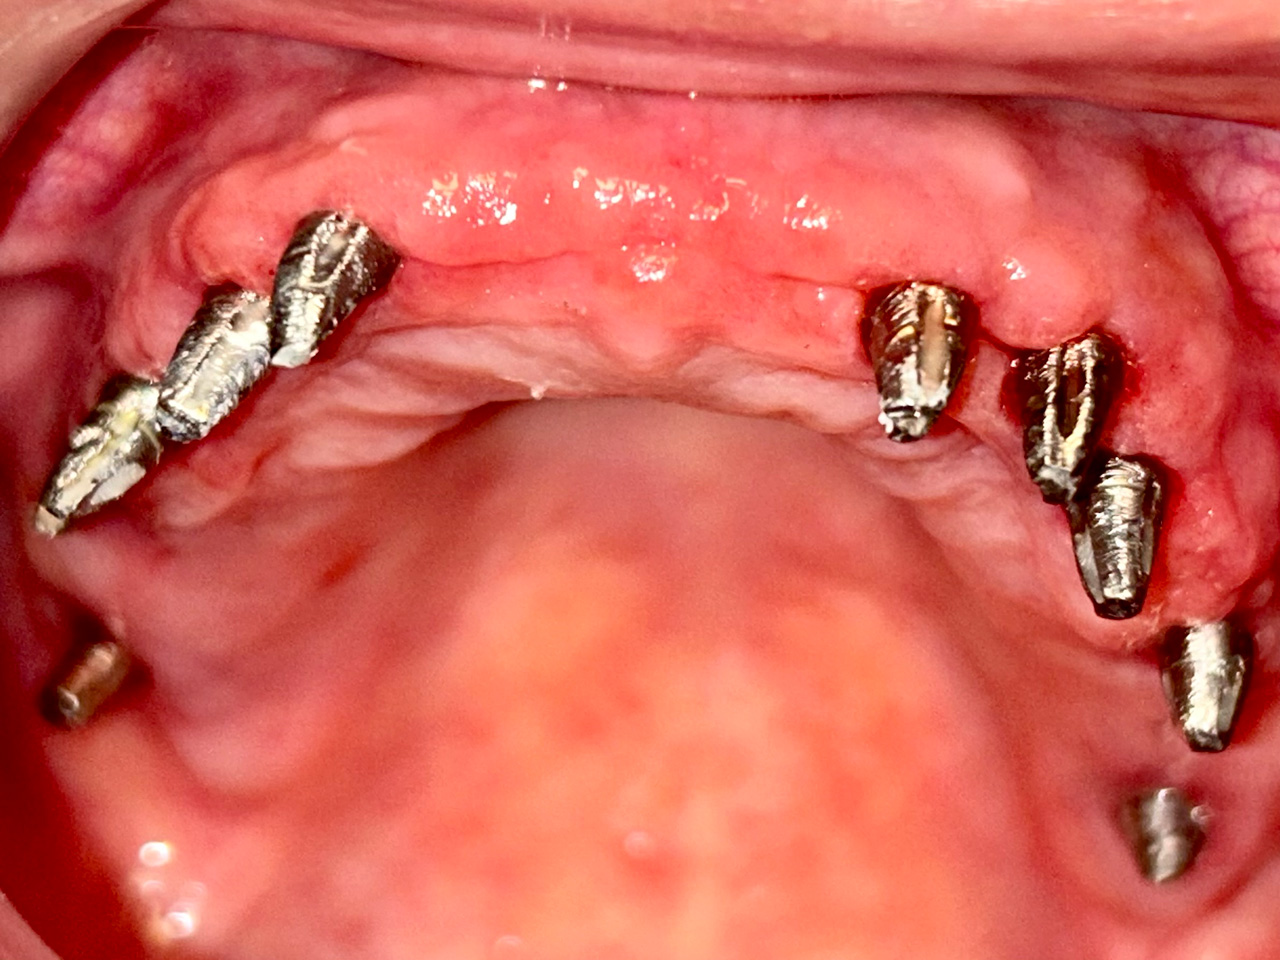

Elhanyagolt fogsor cseréje 2 nap alatt

2 nap alatt varázsoltuk ezt a szép esztétikus alsó, felső körhídat implantátumokkal megtámasztva a korábban elhanyagolt szájba. Az 1. nap 26 fogat távolítottunk el, mert annyira rossz állapotban voltak, és rögtön azonnal terhelhető IHDE svájci implantátumokat raktunk be, fentre 8, lentre 6 darabot. A sebeket összevarrtuk és intraorális szkennerrel digitális lenyomatot vettünk. 2 nap múlva pedig beragasztottuk a kész PMMA műanyag körhidakat. Dr. Kelemen Péter és a Symbion Fogtechnika munkája.